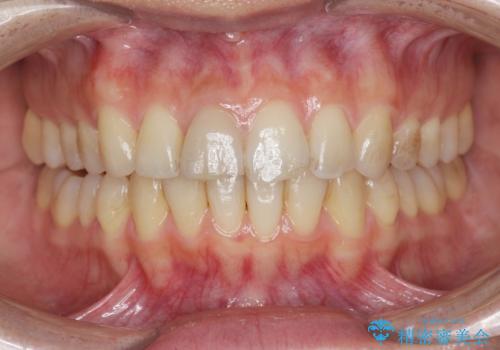

前歯の変色 打撲により失活した前歯の根管・セラミック治療

- 変色してきた前歯の形態回復、色調の改善を求めて来院されました。

X線検査、歯髄(歯の神経)の検査を行ったところ、失活(歯の神経の死んだ状態)であると診断されました。

放置すると変色が進行するだけでなく、根尖病変も形成される恐れが強いことから、根管治療を行ったのちセラミッククラウンによる審美性の改善を計画します。

自然な色調をセラミッククラウンで再現することができ、審美性の改善に大変喜んでいただくことができました。